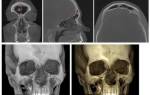

Установить природу новообразования невозможно при внешнем осмотре. Врач проводит дифференциальную комплексную диагностику:

- Рентген позволяет исследовать скелет головы и определить локализацию новообразования.

- Компьютерная диагностика (КТ) выясняет расположение опухоли, размер очага и влияние на соседние структуры.

- На МРТ видна даже самая мелкая остеома. Метод выясняет структуру и плотность очага. По информативности не отличается от КТ.

- Основной этап, определяющий диагноз, занимает биопсия опухолевой ткани для исключения злокачественного процесса.